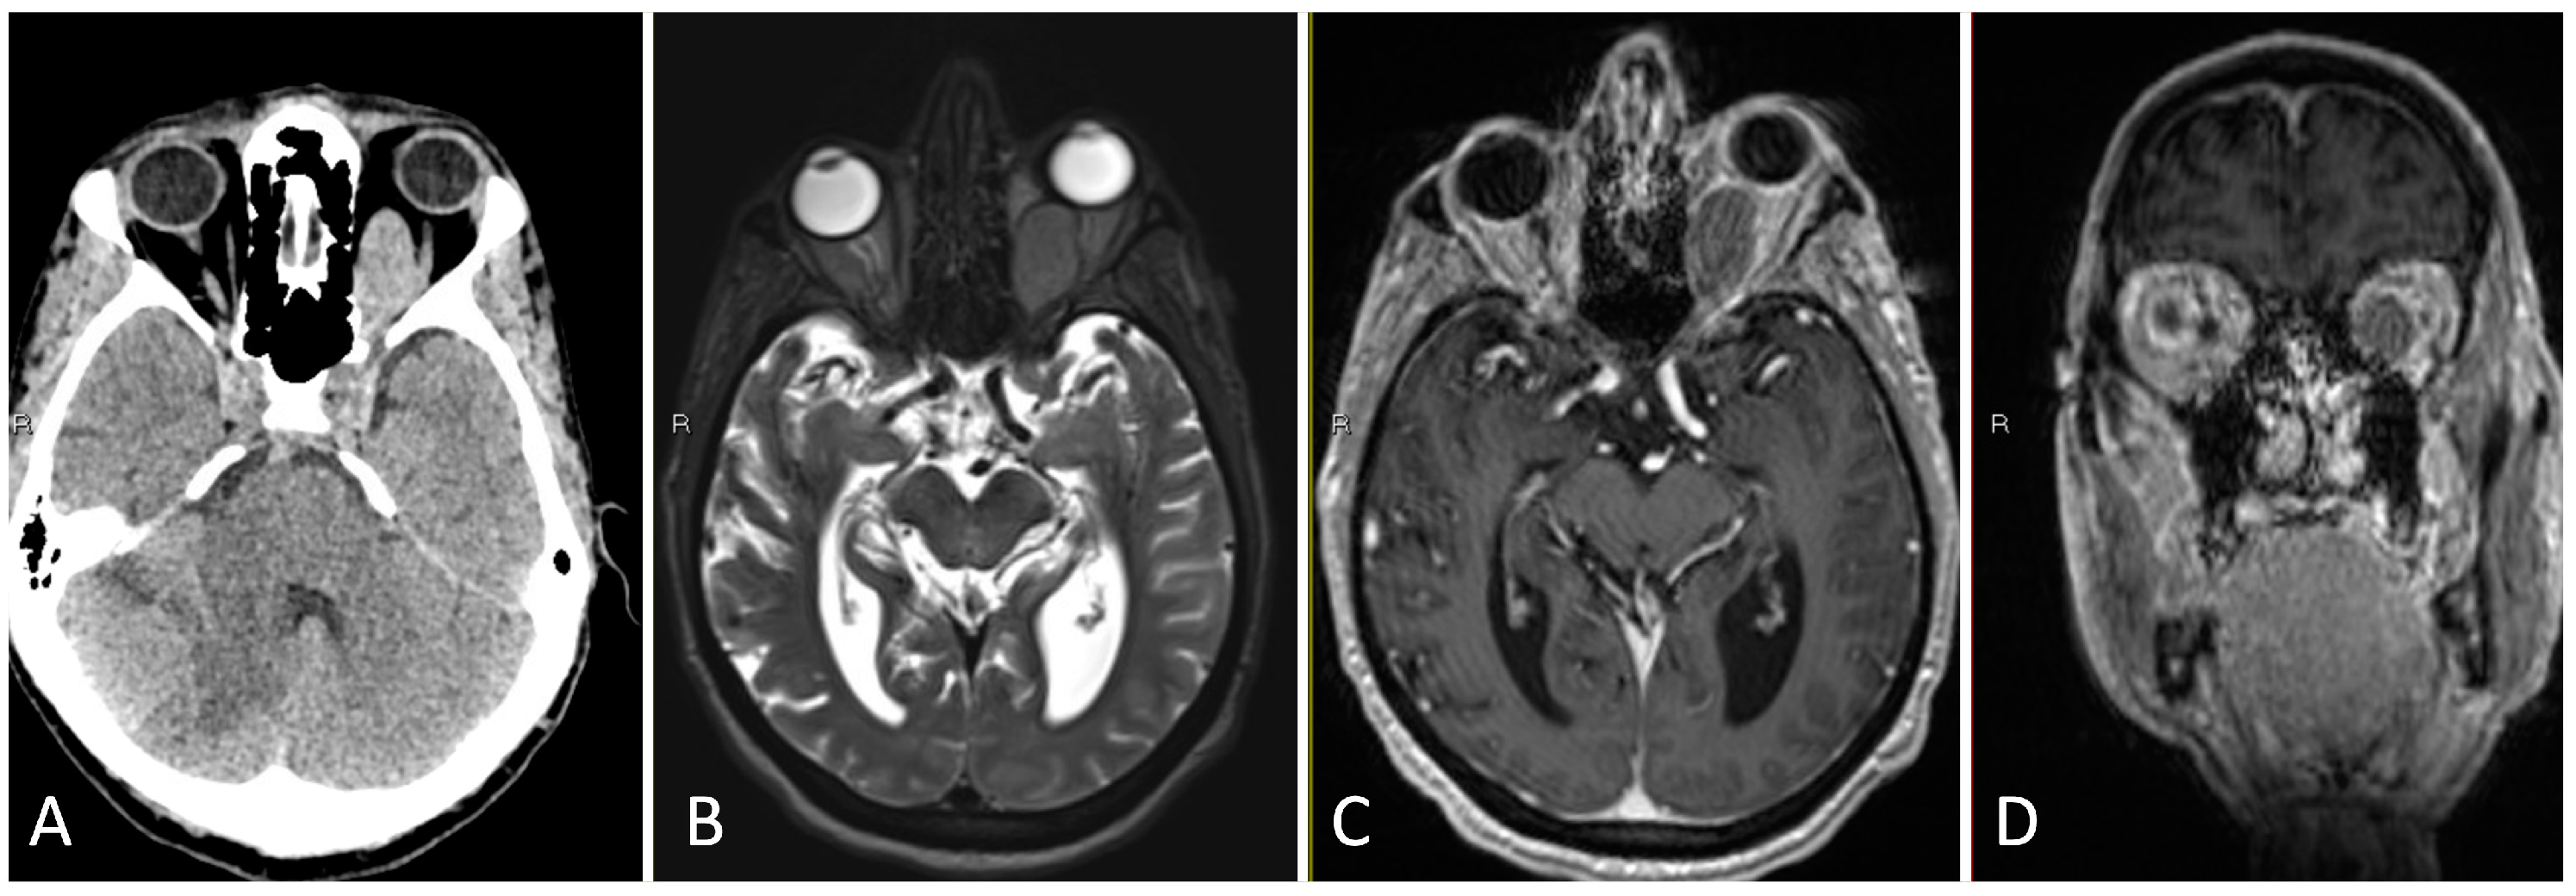

3.1.2. Illustrative Case

3.1.3. Practical Pearls

- An understanding of the osseous anatomy of the nasal corridor, paranasal sinuses, septum, intersinus septations, and relevant vascular structures are of paramount importance in the approach to sellar lesions.

- A pedicled nasoseptal rescue flap may be useful to obtain during the approach to the sellar lesions, particularly in cases of possible CSF leak, and should take into account the horizontal orientation of the posterior septal branch of the sphenopalatine artery.

- Dural opening of Rathke’s cleft cysts, one should begin anteriorly and inferiorly to minimize the risk of inadvertent CSF leak and iatrogenic injury to the pituitary gland.

- One must be mindful of diaphragm downward migration and identification during cyst resection to avoid a CSF leak.